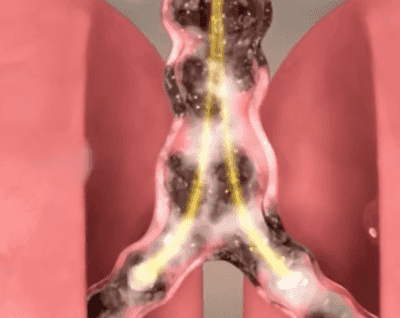

【止咳潤肺】麥冬枇杷葉雪梨片

0f8fdf4f52dae4528e552b95ecf515f1.gif